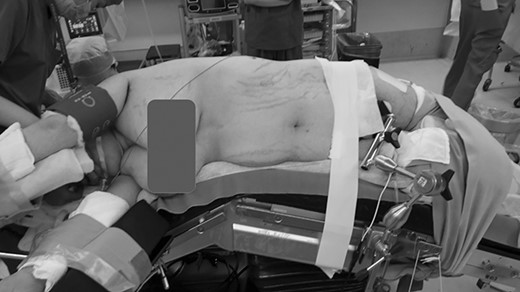

A 42-year-old woman with a body mass index of 38.4 kg/m2 was consulted by an endocrine surgeon with a chief complaint of right buttock pain after awakening from anesthesia. The patient underwent laparoscopic tumor resection for a left nonfunctioning adrenal tumor under general anesthesia by endocrine surgeons. The patient was placed in the right lateral jackknife position (Fig. 1). The operative time was 5 h 37 min, and the anesthesia time was 8 h 15 min. After awakening, the patient complained of right buttock pain. A 12 cm long erythema centered on the right greater trochanter was observed. There was no paralysis, sensory disturbance and circulatory disturbance of the lower extremities. The patient was diagnosed with bursitis at the greater trochanter and was followed up for observation. Postoperative pain management was performed using transvenous self-regulated analgesia.

Lateral jackknife position. The right buttock is at the apex, supporting the patient’s weight. However, this is an intraoperative photograph of a patient different from the one shown here.

Recently, Adib et al. conducted a systematic review and meta-analysis of 139 cases, including those from their institution [3]. The most common etiology was postoperative, although the etiologies included heavy drinking, prolonged use of the same position owing to drug use, traumatic injury and medical etiology. The surgical position is another known risk factor for GCS. The lateral position was the most reported, followed by the supine and prone positions. In the lateral position, the dependent buttock region is subjected to greater direct pressure, which is a known risk factor [4, 5]. In this case, the patient was in a lateral jackknife position (Fig. 1), which places pressure on the buttocks and is considered a significant risk factor.